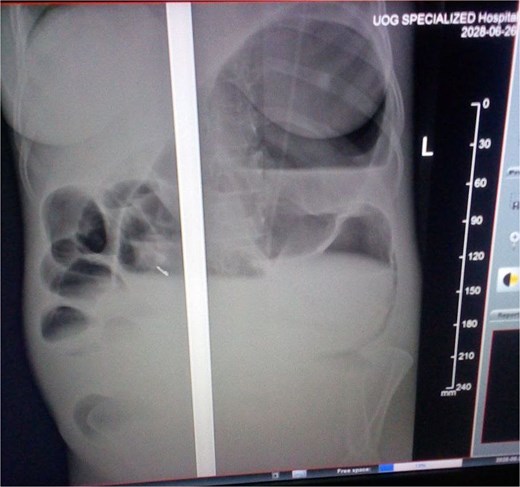

Laboratory investigations, including complete blood count (CBC), electrolytes, and organ function tests, were within normal ranges. A plain abdominal X-ray demonstrated bowel loops extending from the right lower quadrant to the left upper quadrant, with a paucity of air in the distal segment and peripheral air-fluid levels (Fig. 2). A differential diagnosis of large bowel obstruction, possibly secondary to gangrenous cecal volvulus, was considered.

Abdominal X-ray showing the dilated colon and multiple air-fluid levels.